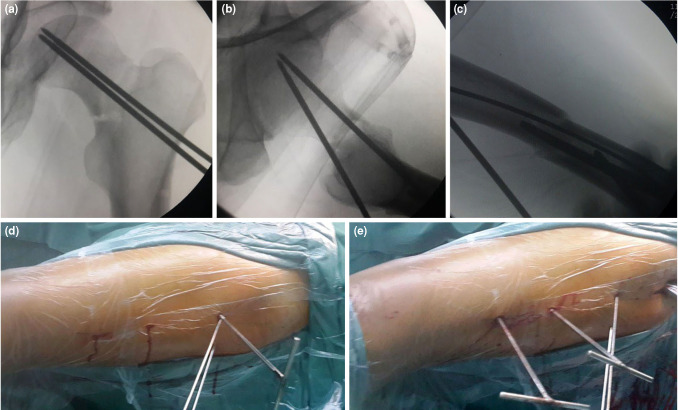

Patients and methods: Between January 2013 and December 2021, a total of 25 adult patients (19 males, 6 females, mean age: 32.8±10.9 years; range, 19 to 57 years) who sustained concurrent ipsilateral femoral neck and shaft fractures were included. The patients underwent internal fixation using a reconstruction nail with the assistance of a reductor-T tape pin, employing percutaneous techniques. The operation time, reduction time, fluoroscopy time, blood loss, preoperative and postoperative Visual Analog Scale (VAS) scores, fracture union time, Harris scores of the healthy and affected sides after fracture union, complications and lower limb functional outcomes two years post-surgery were recorded.

Results: All patients underwent successful surgery with the assistance of the reductor-T tape pin using percutaneous techniques without the need for open reduction. The mean operation time from skin incision to wound closure was 80.0±15.0 (range, 55 to 105) min. The mean fracture reduction time was 22.0±4.0 (range, 15 to 28) min. The mean fluoroscopy time was 16.0±3.8 (range, 9 to 25) sec. The mean blood loss was 335.0±142.0 (range, 150 to 550) mL. The postoperative VAS score of the affected limb was significantly lower than the preoperative score (p<0.01). The mean healing time of femoral neck fractures was 4.0±0.3 (range: 3.2 to 4.8) months. The mean healing time of femoral shaft fractures was 4.8±0.9 (range, 4.1 to 7.5) months. All patients were followed for over two years. No cases of delayed healing of femoral neck fractures or femoral head necrosis were observed. However, delayed union of femoral shaft fractures occurred in three patients. There was no statistically significant difference in Harris scores between the affected and healthy sides at the time of fracture healing (p>0.05).

Conclusion: The use of a reconstruction nail assisted by the percutaneous reductor-T tape pin demonstrated successful reduction of ipsilateral femoral neck and shaft fractures, with favorable postoperative functional outcomes. The reductor-T tape pin facilitates the reduction of femoral neck fractures and provides a safe environment for the reduction and fixation of femoral shaft fractures.